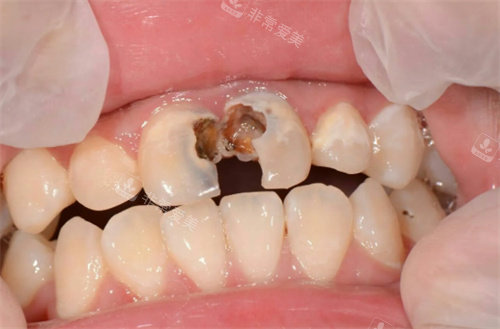

牙齿龋坏图片模型示意图

牙齿龋坏剖面图

牙齿龋坏模型

牙齿龋坏

牙齿龋坏清理图

修复龋坏的牙齿